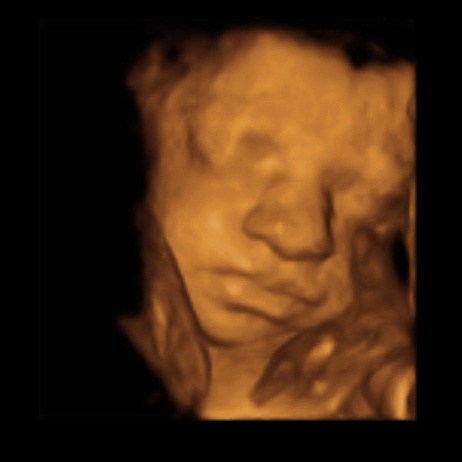

Går det ellers godt med graviditeten?